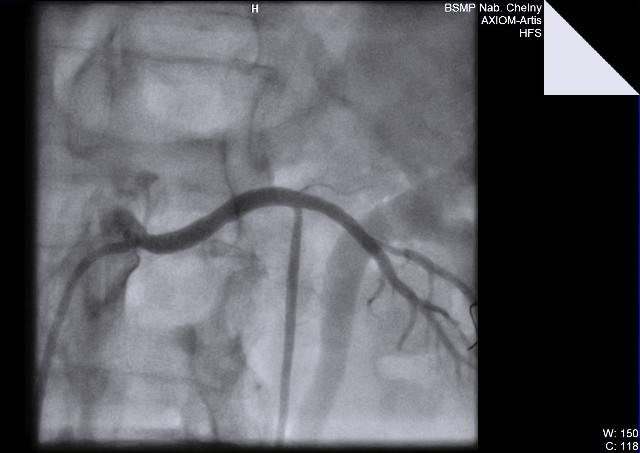

06.09.11. г. Выполнена ангиография ветвей дуги аорты, почечных артерий.

Диагноз: Генерализованный атеросклероз. Атеросклероз брахиоцефальных артерий. Стенозы внутренних сонных артерий слева 60%, справа - 50%, устья позвоночной артерии справа 70%. Сосудистая мозговая недостаточность II ст. Атеросклероз висцеральных ветвей аорты. Стеноз почечной артерии слева 70%. Синдром вазоренальной гипертензии. Синдром Лериша. Стенозы ОПА 85%, НПА 75% справа. Окклюзия НПА слева. Облитерирующий атеросклероз артерий нижних конечностей. Бедренноподколенное шунтирование справа в 1997 г.(шунт окклюзирован). Стеноз ОБА 60%, окклюзия ПБА, ПКА, берцовых артерий правой нижней конечности. Стенозы ОБА – 65%, ГБА 50%, ПКА 60%, окклюзия ПБА, берцовых артерий левой нижней конечности. ХАН нижних конечностей III степени.

06.09.11. БСМП г. Набережные Челны выполнено одномоментное стентирование устья правой позвоночной артерии, левой почечной артерии